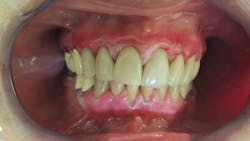

Lichen planus pemphigoides (LPP)1 is designated as a combination of lichen planus and bullous pemphigoid, or mucous membrane pemphigoid2 (figure 1).

One of the theories behind LPP is that it initially starts as lichen planus. As the proteins from the basement membrane region become increasingly exposed as a result of chronic inflammation and damage, autoantibodies develop against one of these proteins (figures 2, 3).